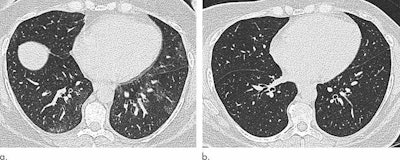

Axial unenhanced inspiratory CT images of the lungs of a 51-year-old woman before (a) and six months after (b) bariatric surgery that led to a 31-kg (68 pounds, or nearly five stone) weight loss (body mass index fell to 36.1). The mosaic attenuation seen before surgery was resolved after surgery. (Images courtesy of Dr. Susan Copley and Radiology).Copley also referred to a study she and a team conducted last year that was published in Radiology that used CT to assess lung parenchymal and tracheal morphology before and six months after patients underwent bariatric surgery. This investigation showed that particular imaging abnormalities improved after patients lost weight.

| Mosaic attenuation | 33.3% | 13.7% |